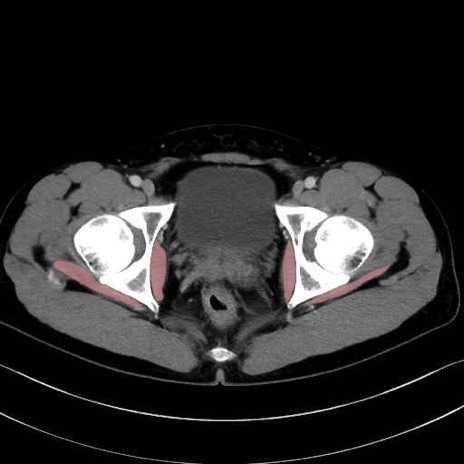

内閉鎖筋 (Obturator internus)